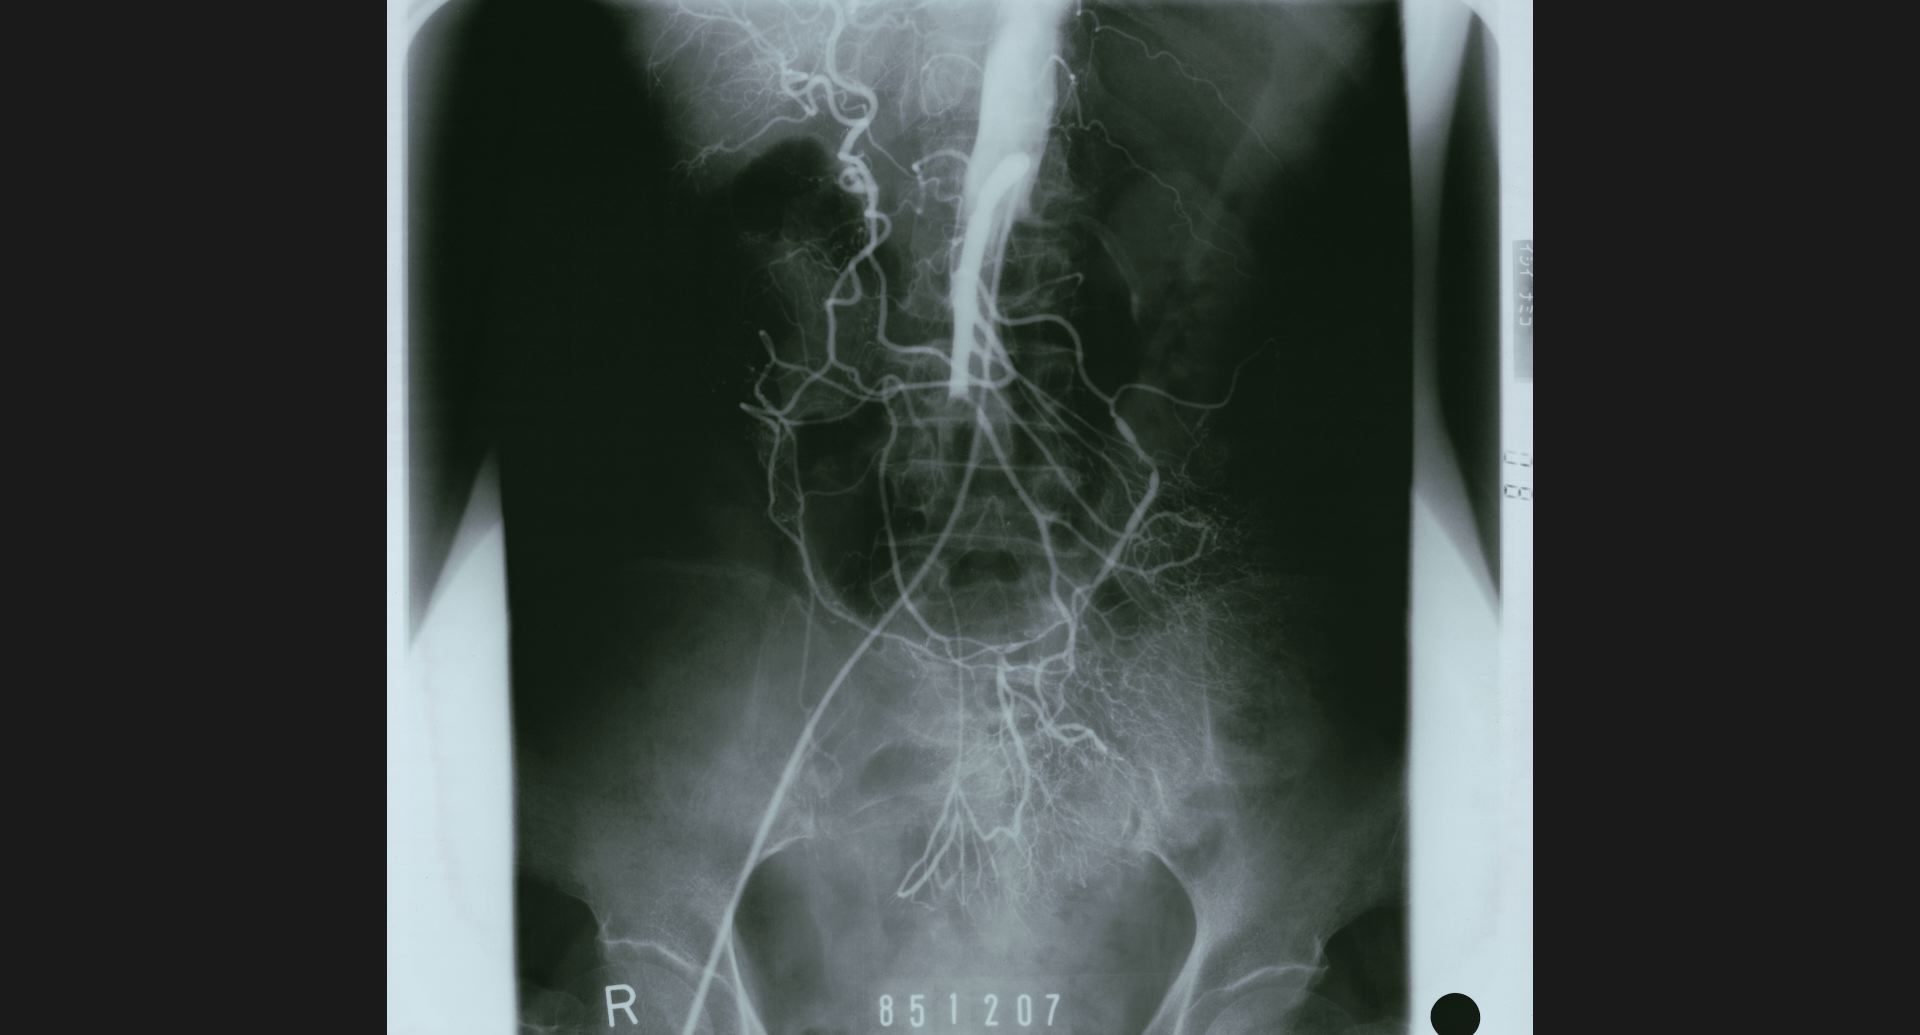

fig.13(151KB) :Aortic aneurysm (DSA)